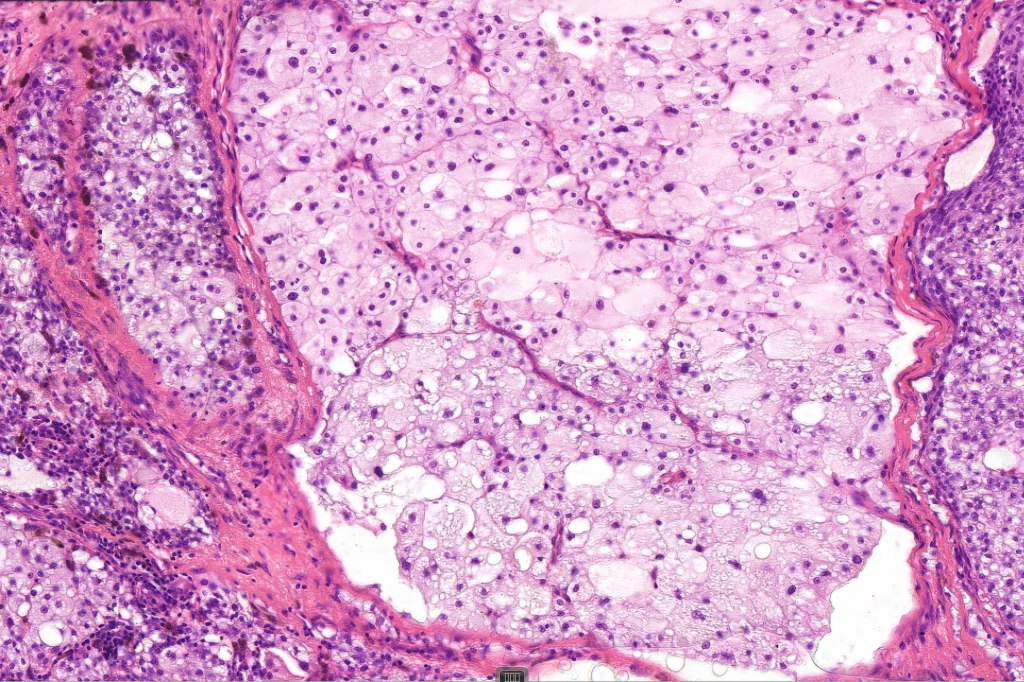

Histological features

•May affect the tumor in part or whole

•Enlarged cells with copious eosinophilic, foamy or clear cytoplasm (some authors include melanoma with clear cell change in the same category)

•Variable pigmentation

•Nuclei vesicular or hyperchromatic

•Pleomorphism is not generally marked and indeed can be very subtle